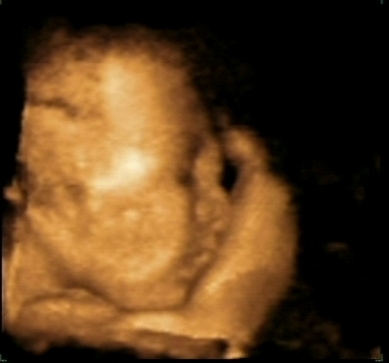

De ultrahangon megneztuk a mokust, olyan cukin dobogott a kis szive.

Mentek holnap 4d-re? De jooooo! A kepeket minel elobb rakd majd fel!! Mi anno Bercellel a 24. heten voltunk, es szerintem egy az egyben ugy nezett ki Bercel 1 hetesen, mint a 4d-s kepen, ha megtalalom, mindenkepp felteszem a ket kepet egymas melle (bar szerintem a topicban is itt van valahol, lehet hogy eloszor itt nezek szet...)